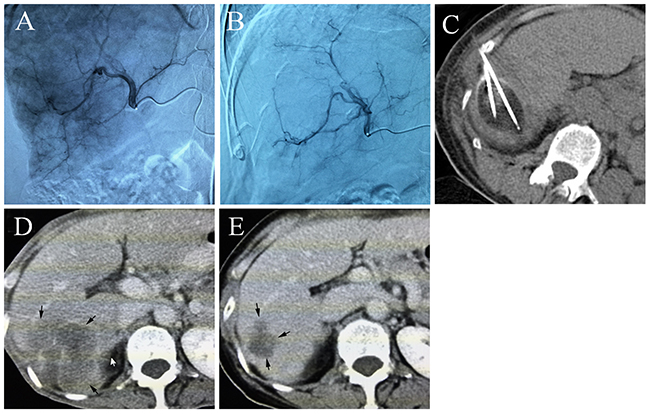

Four to six weeks after treatment, 5 patients and 7 patients with residual active tumors were identified in the DEB-TACE-Cryo group and Cryo group, and the intervention success rates were 82.7% (24/29) and 77.4% (24/31), respectively. All 8 patients with residual active tumors underwent a second cryoablation cycle (Figure 1). Six months and 1 year after treatment, there were 5 and 11 cases with local recurrence or distant metastasis in the DEB-TACE-Cryo group, respectively. This recurrence rate represents 17.2% and 37.9% (7 local recurrence and 9 distant metastasis), respectively. In the Cryo group, there were 7 cases and 21 cases with local recurrences or metastases, and the recurrence rates were 22.6% and 67.7% (8 local recurrences, 13 distant metastases), respectively. The difference in the recurrence rate of the two groups one year after treatment was statistically significant (P = 0.0207).

Figure 1: (A) Common artery angiography of a 65 year old male patient with HCC, selective catheterization of the pathologic branch of the right hepatic artery supplying the tumor, (B) the artery angiography shows that most of the tumor staining disappeared after DEB-TACE, (C) percutaneous cryoablation under CT guidance, an ice ball was formed, (D) the contrast-enhanced CT scan shows a huge tumor before treatment, (E) five months after DEB-TACE-Cryo treatment, the enhanced CT showed that the tumor was significantly reduced.